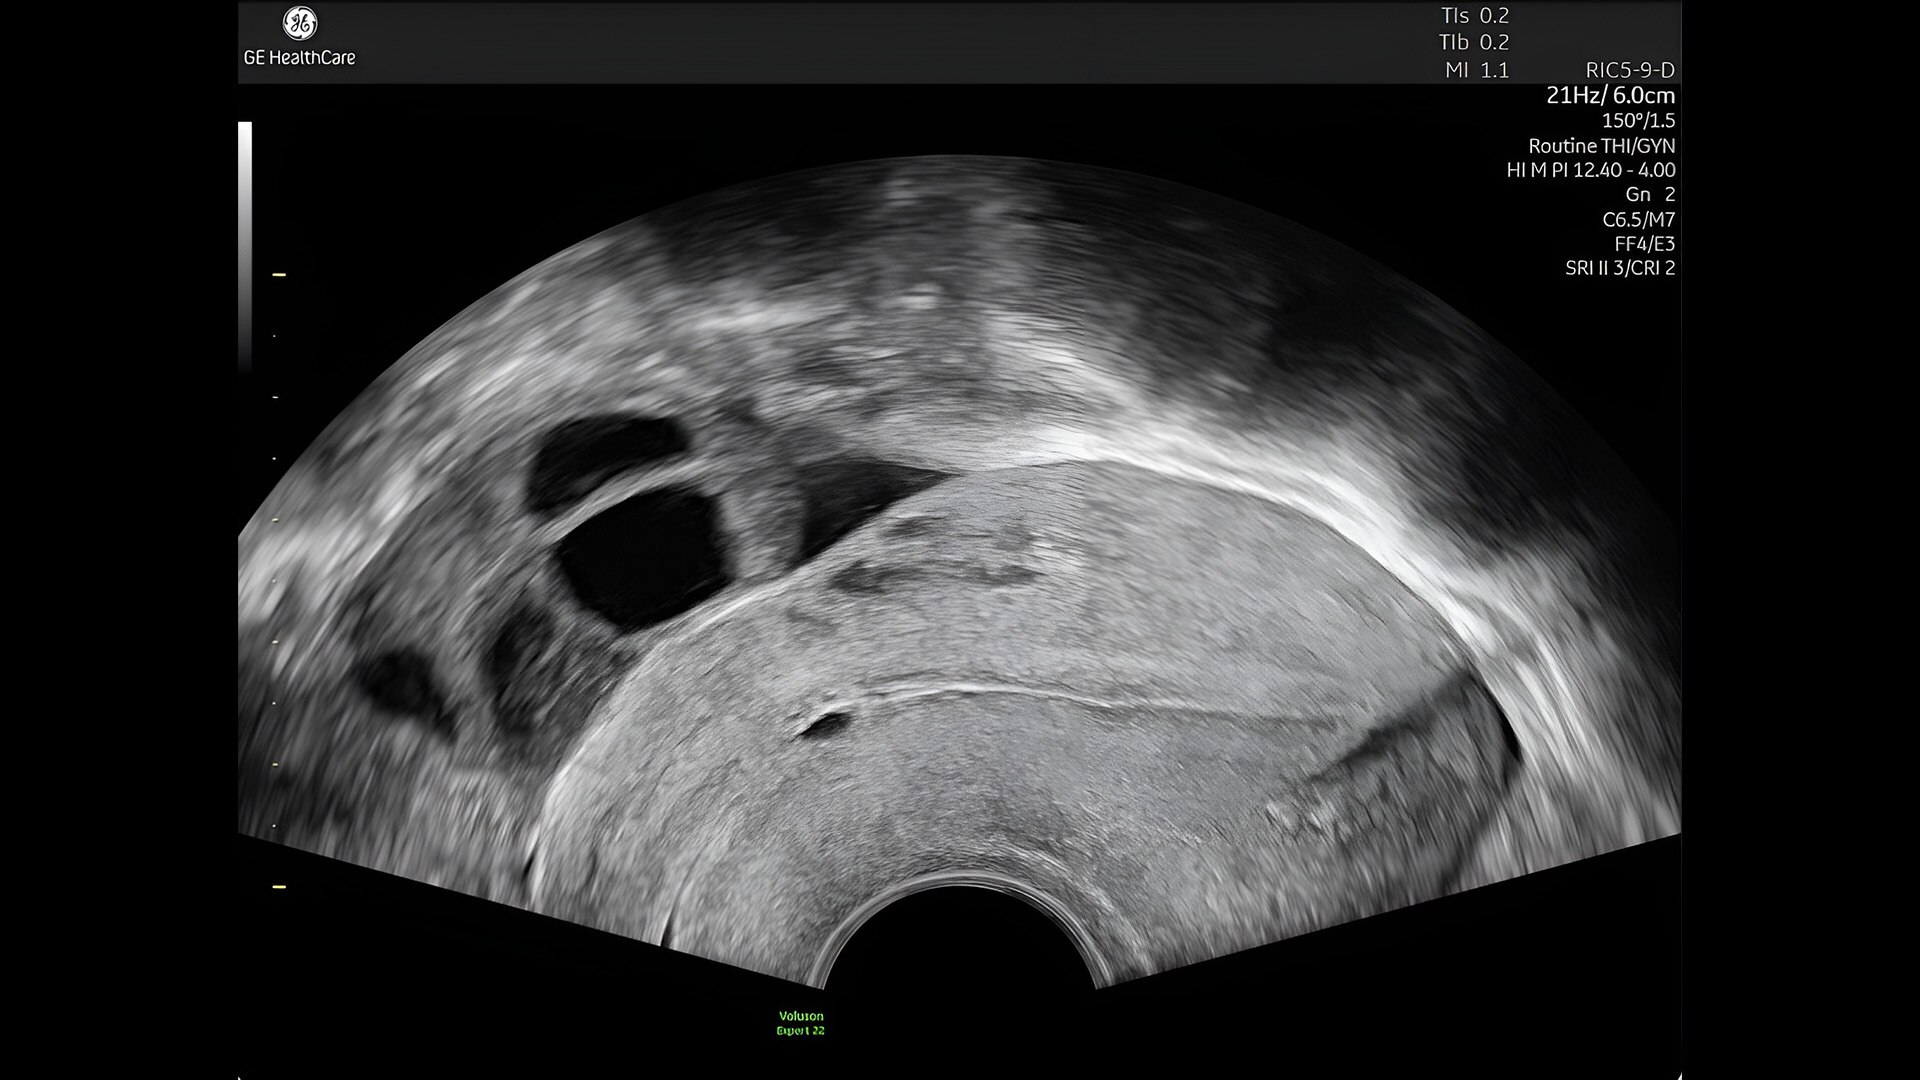

Pelvic health

Offer patient answers faster with Ai-based automation tools

Complex cases come with enough uncertainty. That's why the Voluson Expert 22 is specifically designed for in-depth assessment of complicated anatomy — with pioneering first trimester, fetal cardiac, gynecological, and other pivotal technologies that focus on early detection and intervention.